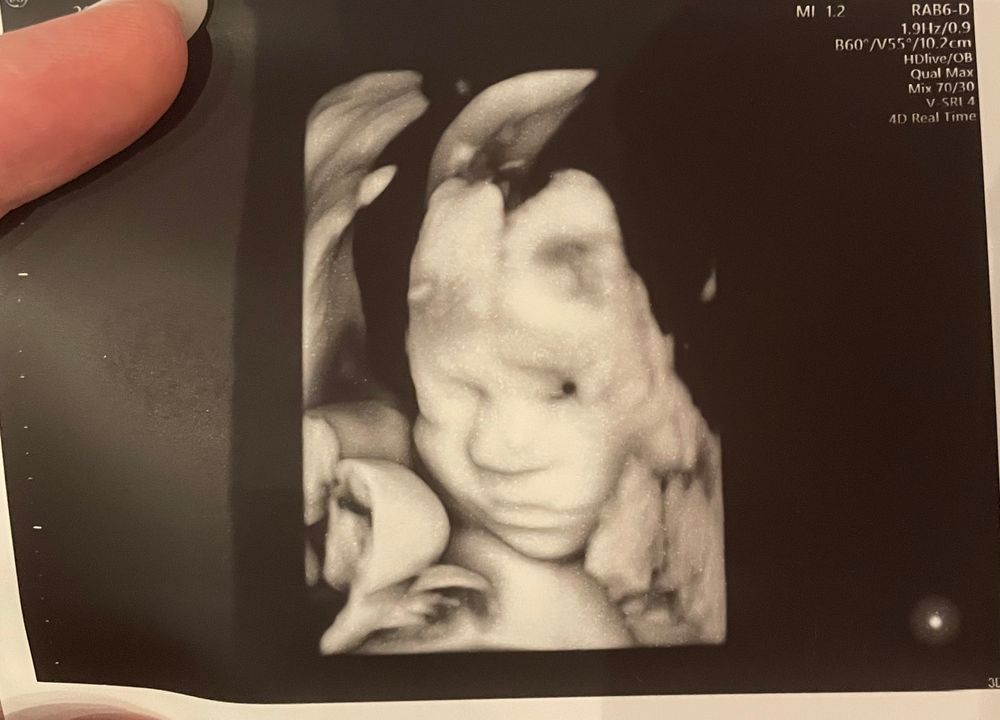

Sassa , я всегда делаю в клинике где веду беременность, а фото просто прошу распечатать) моя Узист всегда перед цервикометрией смотрит ребенка, измеряет сердце и количество околоплодных вод, отдельно за это на плачу.

Как же хорошо когда всё хорошо 🤗💖